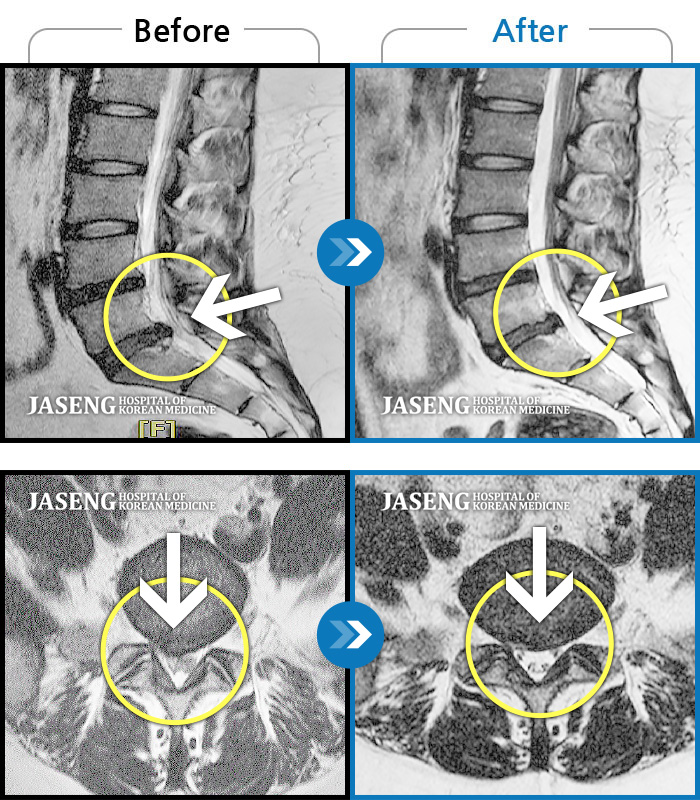

허리디스크

인천 · 강아현 원장

좌측 허리 통증 및 골반 통증이 심하여 걷는 것도 힘든 상태로 내원하셨습니다.

촬영시기

2024.05.08 ~ 2025.11.12

2025.11.14